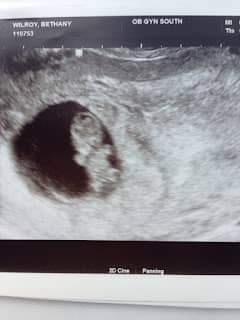

An ultrasound picture of a 12 week old fetus.

Our firstborn child was due on August 31, 2016.

From the very first day I was injured, people questioned whether I would ever be able to have children. That question lingered quietly for years. And now, here was the answer—arriving on the very same date that once marked the worst day of my life.

It felt like a whispered response to a question first asked 11 years earlier.